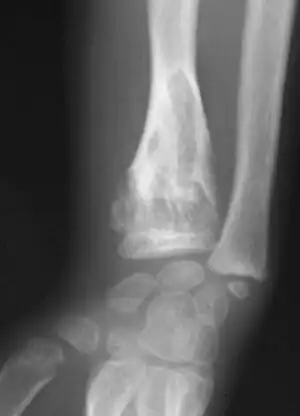

X-ray wrist: Ollier disease in child -

X-ray hand:Ollier disease in child